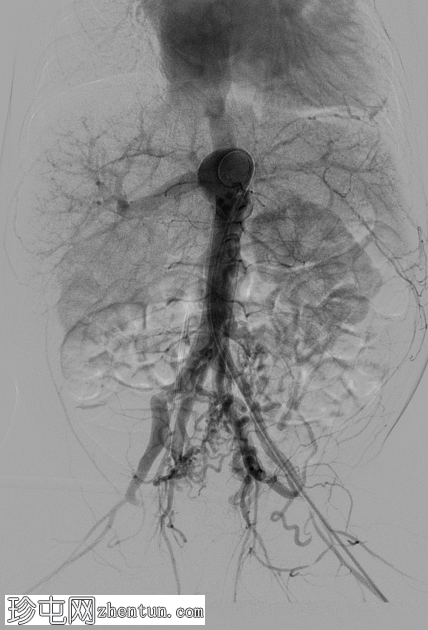

DSA

4.png

额主动脉

注射

5.png

侧主动脉

腹主动脉DSA图像显示脐动脉动静脉畸形,其多条动脉供血血管源自两侧髂内动脉。静脉引流经脐静脉,经静脉导管流入左门静脉,最终返回心脏